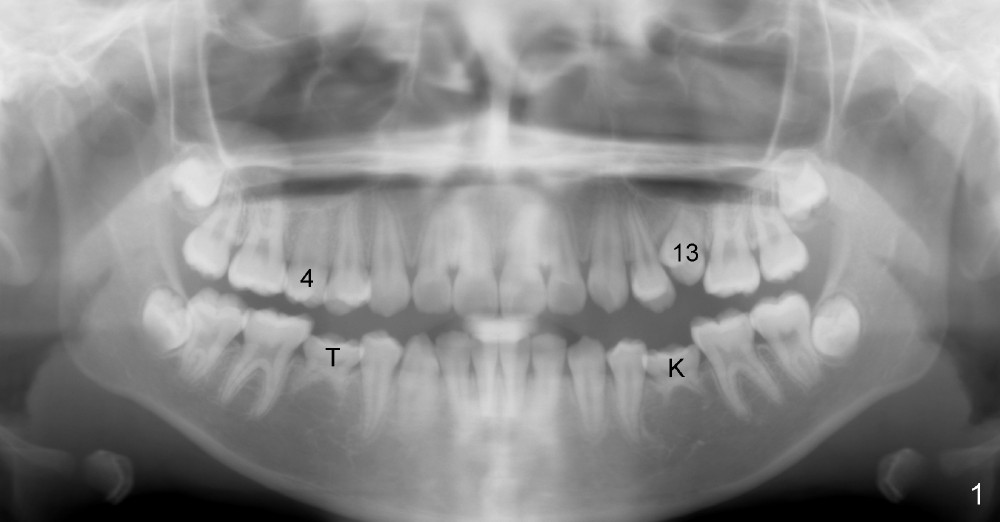

A 13-year-old Asian girl seeks orthodontic treatment for crowding. The lower 2nd bicuspids are congenitally missing (Fig.1,8), whereas the upper right one rotates 180° and the upper left is partially impacted (Fig. 1, 7). The lip muscles strain when the lips close (Fig.3). Orthodontic treatment started with extraction of four affected teeth (#4,13, K and T) 6 months ago. .018' niti wires are being used. Dental midlines do not coincide preop and intraop (Fig.4,4'). Pre-op front view shows that the upper dental midline coincides with the facial one (Fig.1'). There is Class I canine and molar relationship on the right (Fig.5,5',9,9'); open bite on the left (Fig.6,6',10,10').

Next steps: 1. Use elastics to close open bite on the left and to upright #31 (linguoversion, probably #18 to lesser degree) (Fig.8,8',9,9'); 2. Shift the lower midline to the left before closing 2nd bicuspid spaces. What is the best way to close spaces? Power chains for both arches or closed coil springs for upper and loop for lower (which is used for Tiffany Yue)? Since intraop profile is acceptable (Fig.2',3', as compared to Fig.2,3 (preop)), molars will be mesialized.

Update: The left open bite was closed less than one month by wearing elastics between upper and lower teeth (Fig. 6'''). The occlusal plane and midline improve (Fig.4''). Wires have gradually changed to .016x.016, .016x.022 and now .018x.025 with power chains. All the spaces are closed except the one in LR (Fig.7''-10''). What I cannot accomplish is to fix meisal (Fig.5'' (white line), 9'') and lingual (Fig.8'' arrows) inclination of LR molars, although elastic is instructed to be placed between UR7 buccal and LR7 lingual. The rectangular wires could be twisted to fix lingual inclination. Which should be done first: LR space or LR molar inclination? Click each figure for magnification.